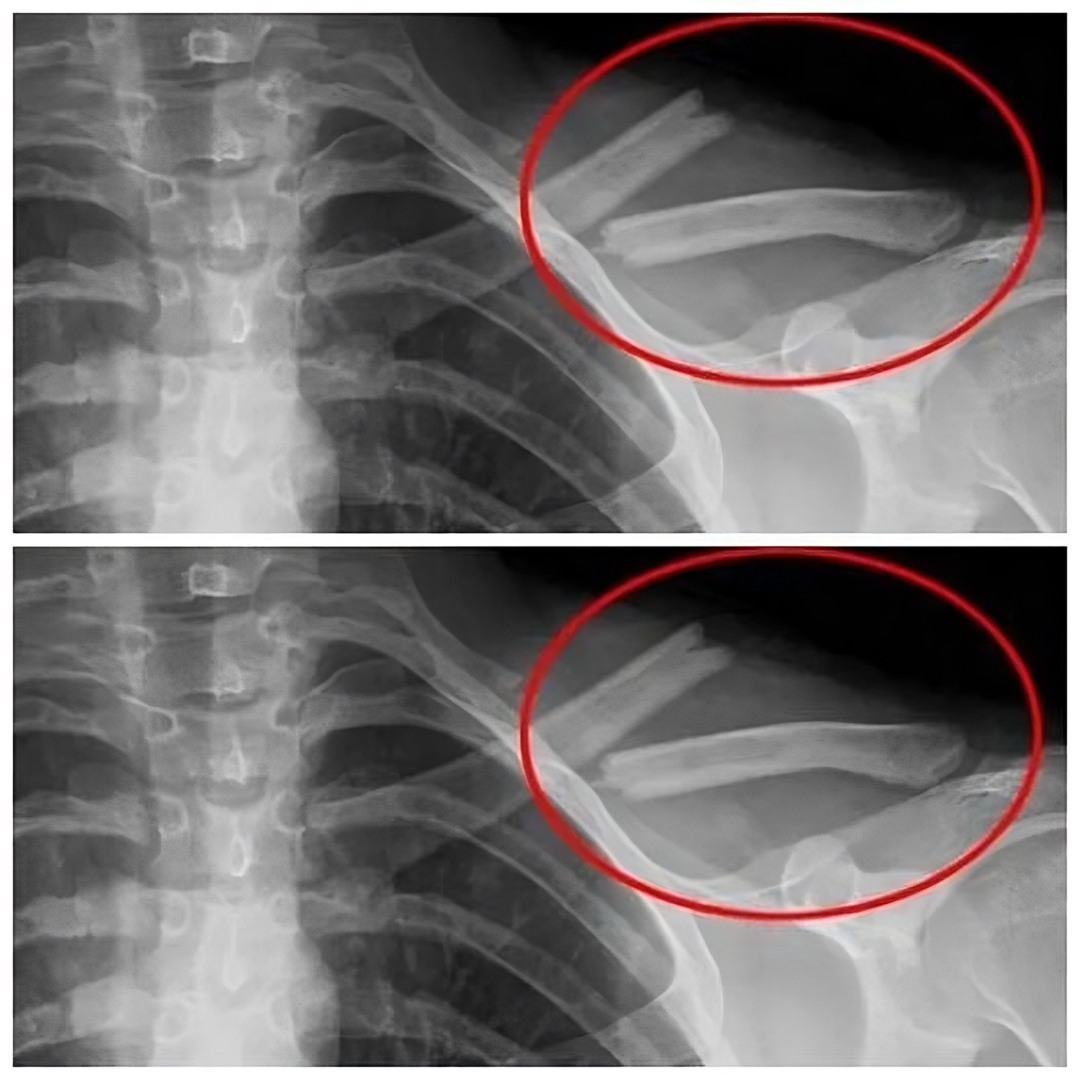

The phosphoric acid found in these beverages can disrupt the delicate balance of calcium in the body, leading to the leaching of this essential mineral from the bones. Over time, this can result in weakened bones, increased risk of fractures, and the development of conditions such as osteoporosis.

Regular consumption of soda depletes crucial nutrients essential for maintaining healthy bones, potentially leading to chronic damage and progressive weakening over time.